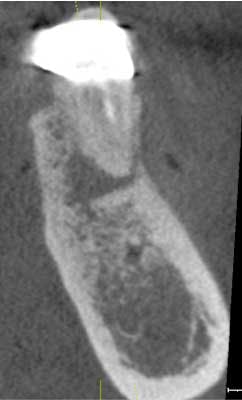

Our implant consultation begins with collecting all the necessary patient information, required legal notices, HIPAA release, etc. Following the initial patient registration, the patient is escorted to our in-house cone beam CT scanner to obtain a full-mouth 3D CBVCT. I highly recommend a full-mouth scan for multiple reasons. First, I believe in comprehensive examinations and diagnoses. As an oral health-care provider, I am responsible for all structures between the left and right buccal mucosa, oral labial mucosa to oral pharynx, and floor of the tongue to the palatal gingiva. I perform an oral cancer screening, full-mouth periodontal probing, and require full-mouth radiographs for all new patients, regardless of the chief complaint or reason for referral. The full-mouth radiographs are required for a comprehensive diagnoses, and I satisfy this requirement with any of the following: Panoramic X-ray, FMX, or full-mouth CBVCT. I can’t tell you how many asymptomatic periapical lesions or severe periodontal bone loss I have seen on CBVCTs that were not otherwise detectable, but that’s another conversation for another time.

Asymptomatic periapical radiolucency found in the opposite arch of planned implant.